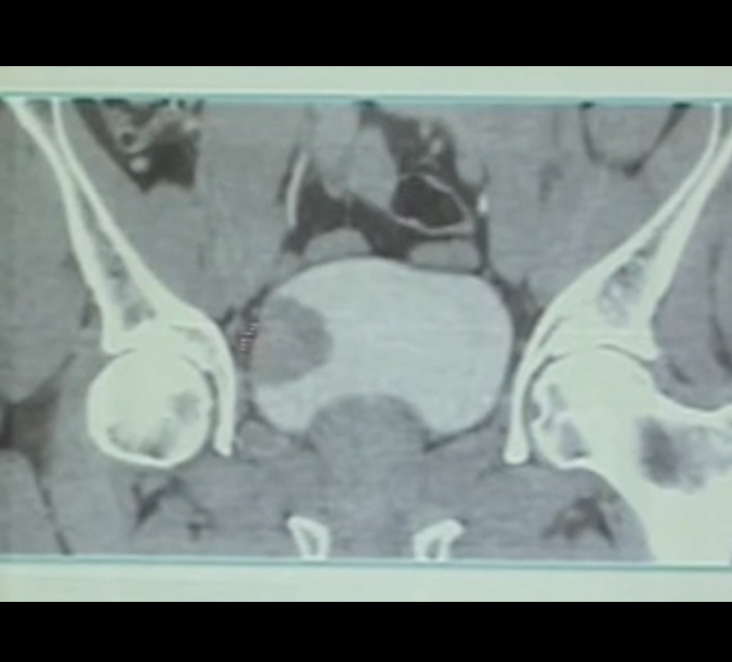

Obturator kick is not infrequently reported during conventional transurethral resection of bladder tumor. Unfortunately, it may end with bladder perforation and hardly controllable bleeding. Herein comes the role of laser ERBT #TURBT #Bladder_tumor #enbloc #erbt #NMIBC